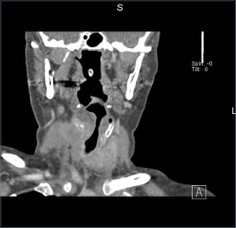

Mujer de 61 años con padecimiento de 1 año de evolución caracterizado por tumor en cuello, disfonía y disfagia progresiva.

Se le realizó tiroidectomía total y laringectomía.

Tumor de células fusiformes con diferenciación semejante a timo (SETTLE por sus siglas en inglés).